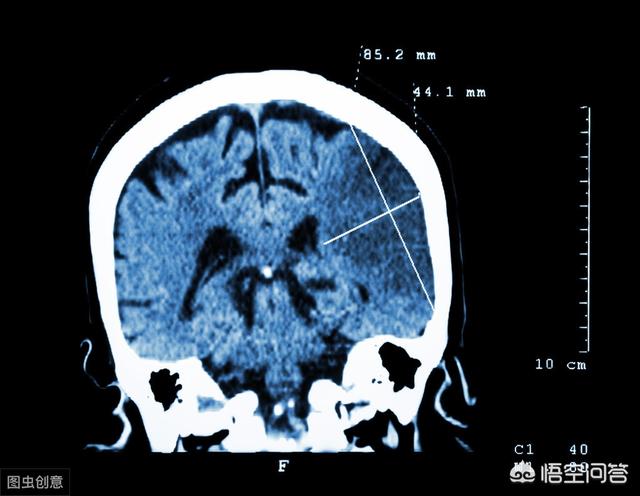

60代のユーさんは昏睡状態にあり、120台の救急車で病院に運ばれた。 病院に到着後、医師は徴候をチェックし、血圧を測定した後、グリーンチャンネルを通して脳のCTスキャンを行ったところ、脳の血管に深刻な閉塞があり、蘇生が間に合わなければ命にかかわることが判明した!

脳CTを撮ったところ、脳血管に深刻な閉塞があり、いつ生命が脅かされるかわからないという結果が出た。

家族は、すぐに120に電話をかけ、医師が到着し、状況の一般的な理解は、すぐに病院に脳CT検査を実施し、結果は脳の閉塞が深刻であることを示している、すぐに血栓溶解療法を実施し、状態がより深刻であるため、最初の脳梗塞発作ではないので、今回は、重症の下に与える。